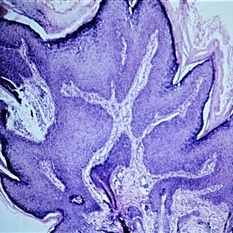

Slide 5-24

Inverted follicular keratosis with thick, acanthotic, folded epithelium and keratin cysts.

Condition/keywords: acanthosis, cyst, epithelium